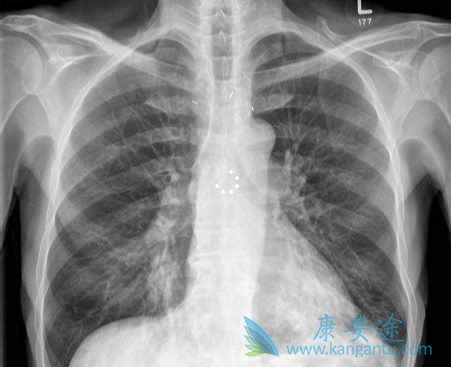

化疗是小细胞肺癌的基本治疗方法。同步放化疗可以改善局限期(LD,即所有病灶都可以包含在一个放射野)患者的生存。具有更广泛病变的患者被归类为广泛期(ED),只能接受化疗。最近在Anticancer Research杂志上发表的一项随机II期临床试验的研究结果在有些方面却与以往的不同。该研究比较了LD 小细胞肺癌的两个不同的胸部放疗(TRT)计划,其目的是探讨基线TNM分期情况,以及N分期之间或N3亚组之间的生存是否有差异。

符合本研究的患者提供CT扫描的基线分期,对所有病理淋巴结转移进行照射,患者完成了TRT和至少一个化疗疗程。N3亚组包括同侧锁骨上、对侧锁骨上、对侧肺门和对侧纵隔淋巴结转移。N3患者较N0-2患者的中位OS显著缩短,但N3亚组之间没有临床相关的生存差异:对侧肺门淋巴结转移:15.5个月,对侧纵隔淋巴结转移:16.7个月和锁骨上淋巴结转移:15.1个月。然而,5年后对侧肺门淋巴结转移者没有患者存活,而锁骨上和对侧纵隔淋巴结转移者存活率分别为6.7%和16.7%。

多个N3区受累患者,中位OS有下降的趋势。一个N3区受累患者五年生存率为20%,而有两个或三个N3区受累患者的五年生存率为0%。T分期之间没有显著的生存差异。T1期肿瘤的中位OS为21.7个月,T2为38.8个月,T3为29.5个月,T4为21.7个月(p=0.356)。多因素分析显示,N3、分期和2-3个 N3区受累是重要的预后不良因素。而基线特征、T分期、胸腔积液或TRT计划均不是独立的预后因素。与N0-2相比,N3的小细胞肺癌生存期显著缩短,但N3亚组之间没有生存差异。因此建议所有N3淋巴结转移应归为LD。